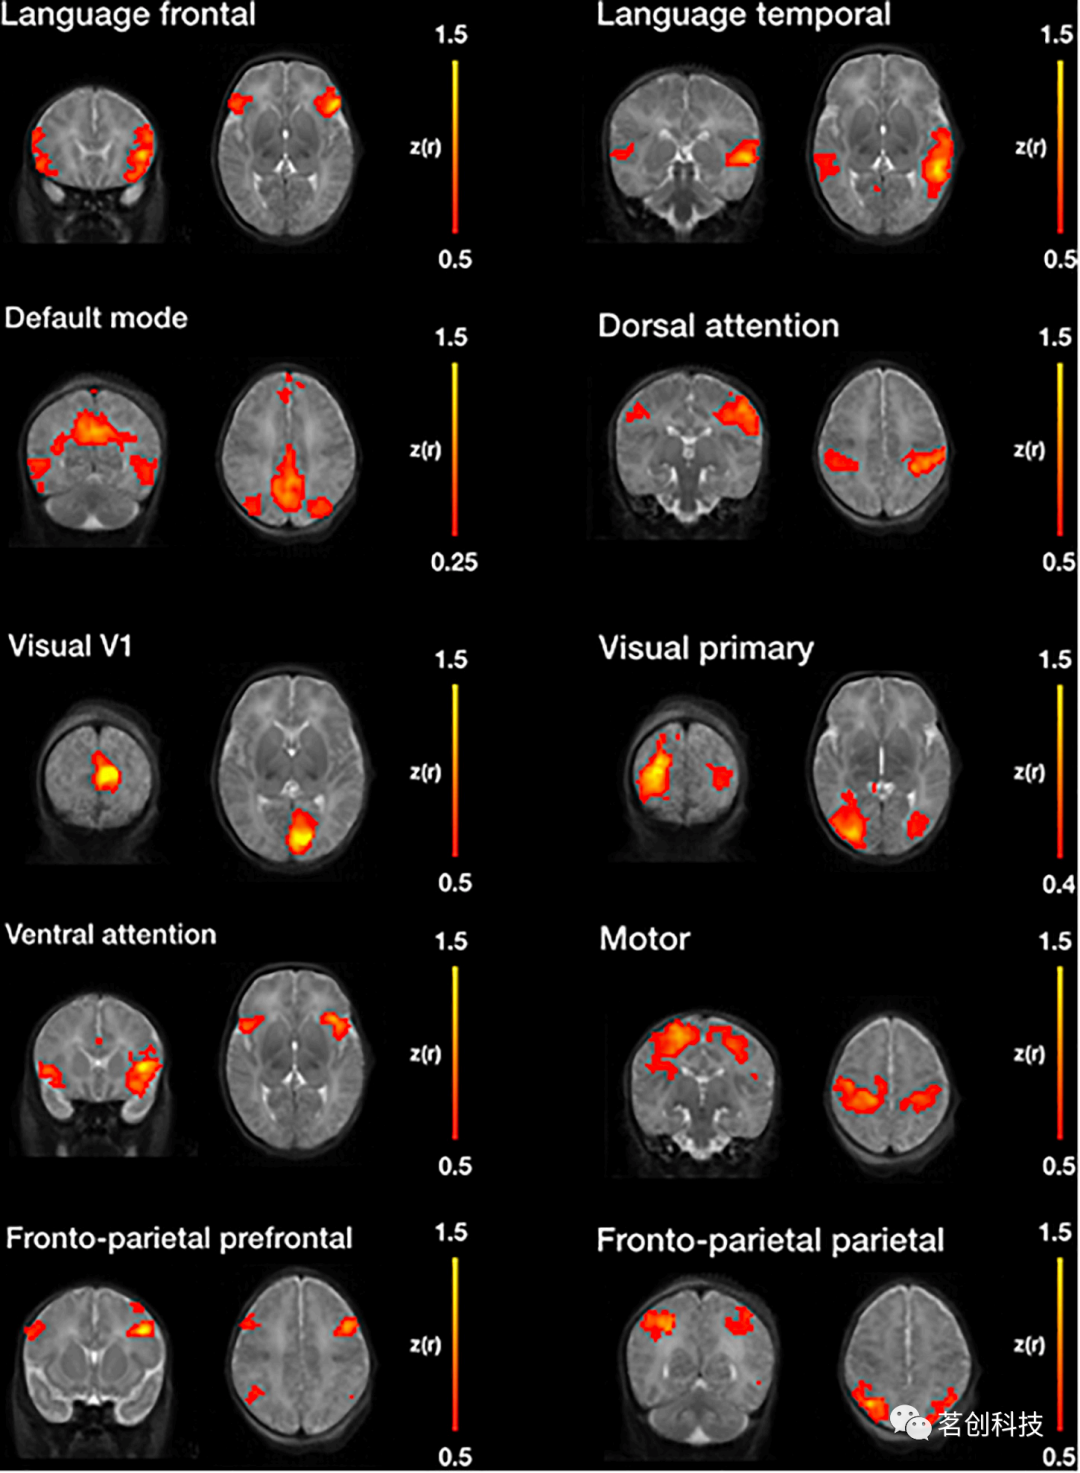

基于种子点的相关性

基于种子点的功能连接确定了ROI(也称为种子)与大脑其他部分之间的相关性。该指标有助于观察与预定义ROI同时激活的区域。NeoRS管道提供31个模板种子,代表一些最常见的静息态网络,包括:语言、默认模式、背侧注意、视觉、腹侧注意、运动和额顶叶网络。可以在文档中找到一个excel文件( Perceptron_ROI_list.xlsx ),其中包含与种子定位相关的所有信息。

静息态网络——基于种子点的相关性

图11显示了采用基于种子点的相关性(SBC)方法进行NeoRS处理后,产生的七个最常见的静息态网络。

图11.使用NeoRS进行图像处理后,通过基于种子点的功能连接获得的静息态网络。